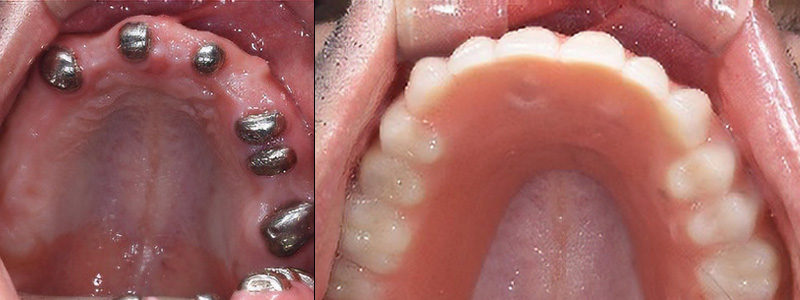

- 治療名

- オーバーデンチャー

- 治療内容

- 残存歯のむし歯治療・入れ歯治療

- 患者様

- 50代男性

- 治療期間

- 4ヶ月

- 費用

- ¥1,067,000

- 治療に対するリスク

- 疼痛

- 執刀医

- Dr.村尾